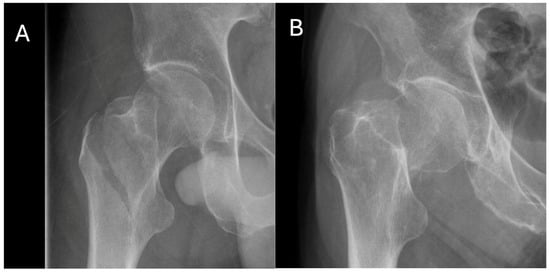

2.2. Imaging and Measurement Tools

2.3. Fracture Classification and Radiographic Measurements